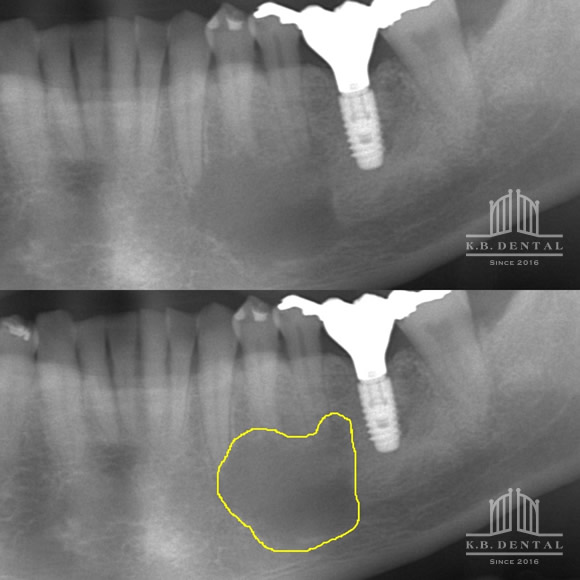

粘液嚢胞摘出 症例2(粘液貯留嚢胞の摘出と同時に行うサイナスリフト)

このパノラマで球状にやや不透過な嚢胞様の画像が確認できます。

CTで見るとくっきりと映ります。

そして手術を行ってまず上顎洞の前壁を取って、シュナイダー膜を明示するとかなり膜に圧力がかかっていて、内圧が上昇しているのがわかりました

穿刺したので内圧が弱まり粘膜が挙上できる様になりました。

穿刺だけでは粘液貯留嚢胞の摘出が不十分なので、最終的にメスで切開して摘出しましたが、シュナイダー膜の先行部分が大きくなったのでメンブレンで封鎖したところです

人工骨を填入して、

縫合したところです。

結局2cc程度内容液を吸引しました。

術前と術後の比較CTです。上顎洞がクリアになって内圧が弱まったので、サイナスリフトした人工骨の吸収スピードも緩徐になります。内圧が高いとどうしても吸収スピードが早まるので、こう言った場合は嚢胞を摘出してサイナスリフトをする方が確実だと思います。

術後のパノラマ画像です。嚢胞の影も消えてます。軟組織に関する手術も神経血管が多くて粘膜だけでなく、時に皮膚にも触れなければならないので難しさはあります。